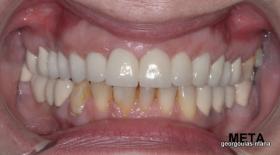

ΟΛΙΚΗ ΑΠΟΚΑΤΑΣΤΑΣΗ ΑΝΩ ΓΝΑΘΟΥ

Η ασθενής ήταν δυσαρεστημένη από την εμφάνιση των άνω δοντιών της. Ήθελε τα δόντια της να αποκτήσουν ομοιόμορφο, πιο λευκό χρώμα κ να αποκτήσει ένα πιο αρμονικό χαμόγελο με φυσική εμφάνιση. Λόγω των εκτεταμένων εμφράξεων σύνθετης ρητίνης στα πρόσθια δόντια, των εμφράξεων αμαλγάματος στα πίσω αριστερά δόντια αλλά και της υπάρχουσας γέφυρας στα πίσω δεξιά δόντια, και σε συνδυασμό με την επιθυμία της ασθενούς για φυσικό αποτέλεσμα αποφασίστηκε η τοποθέτηση ολοκεραμικών στεφανών στα δόντια της άνω γνάθου. Στη θέση του δεύτερου προγομφίου δεξιά τοποθετήθηκε εμφύτευμα. Πραγματοποιήθηκε περιοδοντική θεραπεία, ενδοδοντικές θεραπείες (απονευρώσεις) κ τοποθετήθηκαν ενδορριζικοί άξονες υαλονημάτων όπου κρίθηκε απαραίτητο. Σε όλη τη διάρκεια της θεραπείας η ασθενής ήταν καλυμμένη αισθητικά κ λειτουργικά με προσωρινές αποκαταστάσεις.